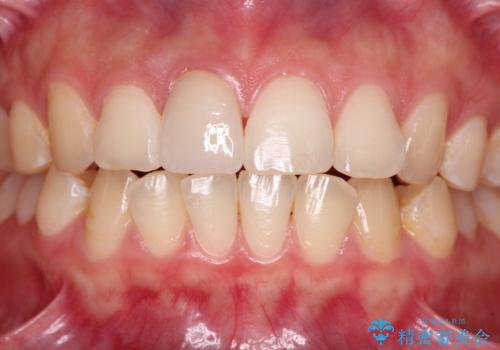

転倒して欠けてしまった前歯をオールセラミッククラウンで自然な口元に

転倒などの強い力がかかった歯は、歯の内部の歯髄組織が壊死してしまったり、外部吸収と知って、歯根の一部が吸収してしまったりと、思わぬ問題を抱えていることがあります。

治療期間においてはこのようなトラブルは発生していませんでしたが、今後も定期的にレントゲン写真撮影などで経過を見ていく必要があります。